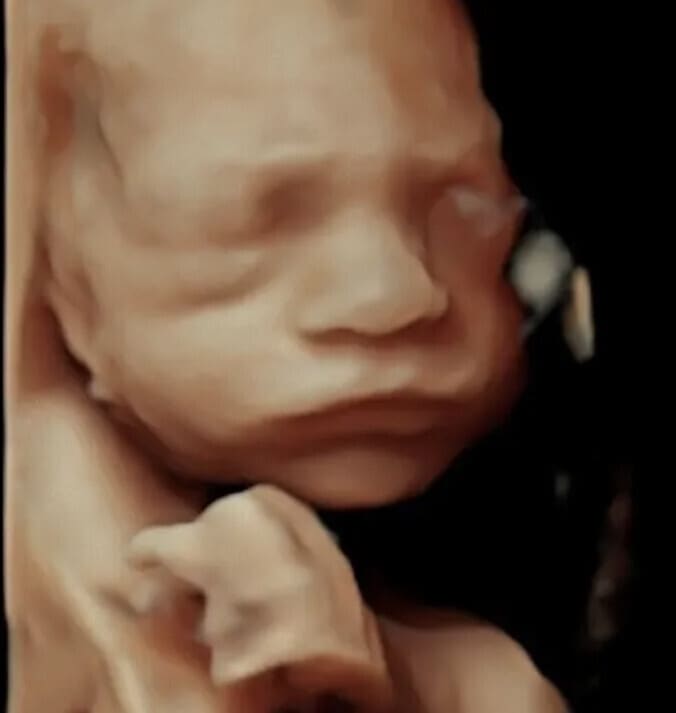

3D 4D HD Baby Scans in North London

✅ Outstanding 4D Baby Scan in 'HD Live'

✅ Super Star Baby-4D Scan in 'HD Live'

✅ 3D, 4D 'HD Live' Scan

✅ Exceptional 4D Baby Scan in 'HD Live'